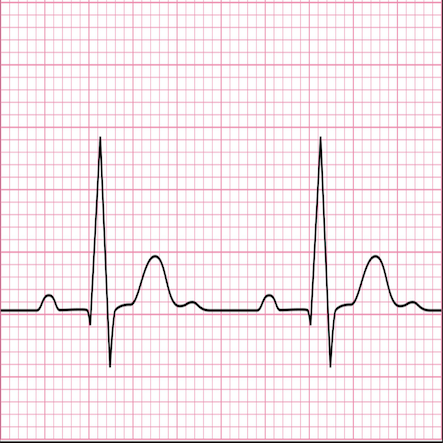

Following clinical assessment, Prof Ruparelia may suggest some investigations to aid reaching a diagnosis and to guide ongoing management. He will always explain what this involves and why they are needed.

Below, please find more information with regards to what the more common investigations entail: